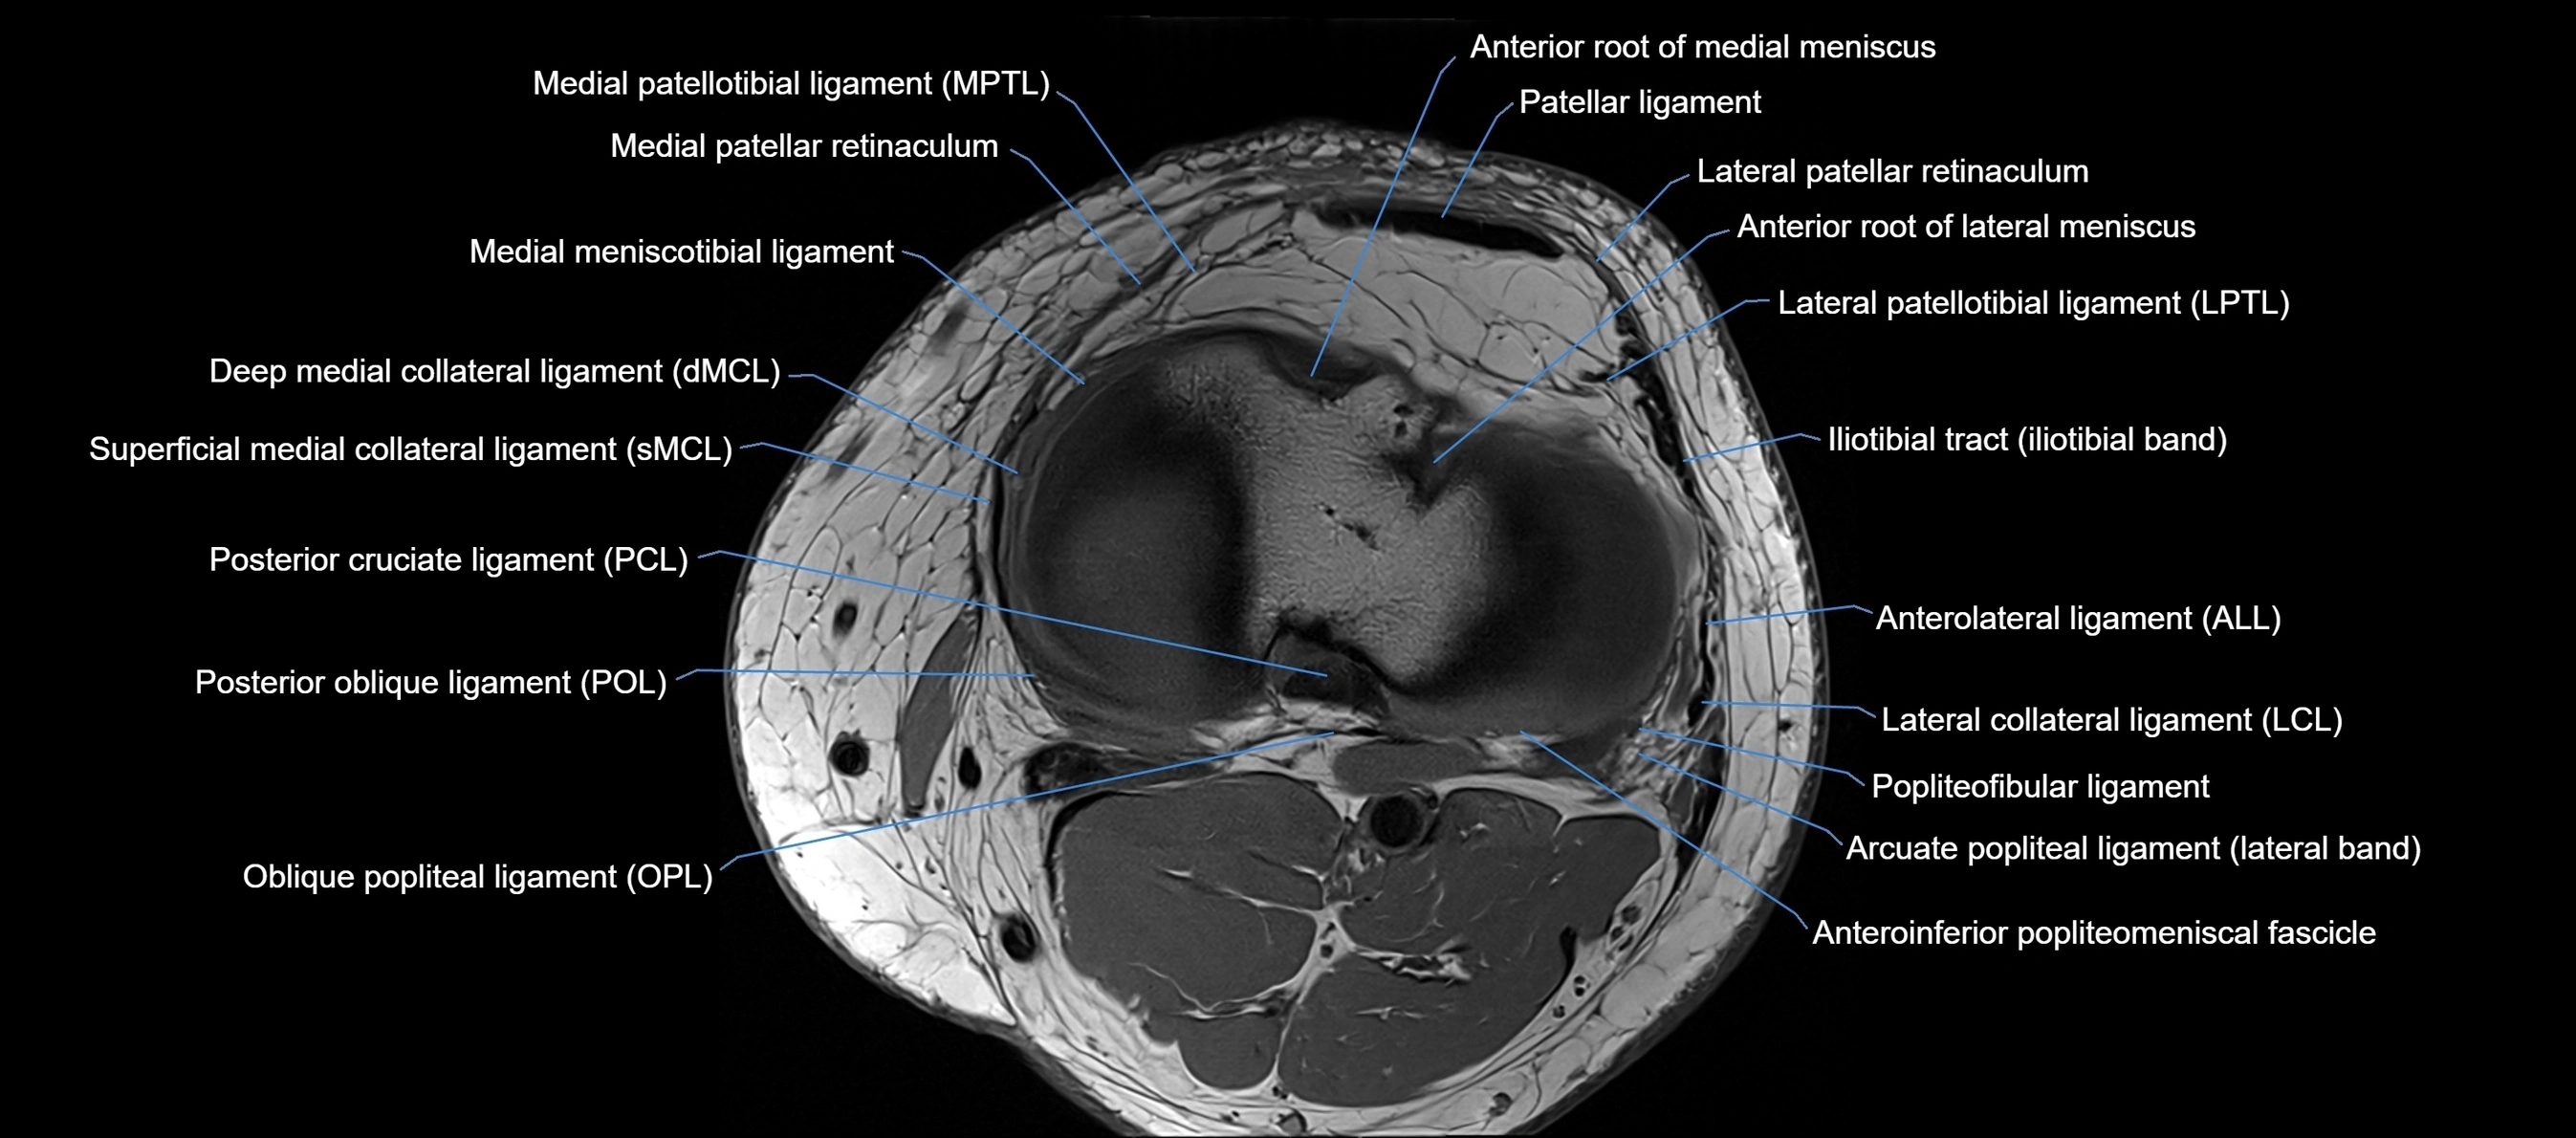

MRI images

image